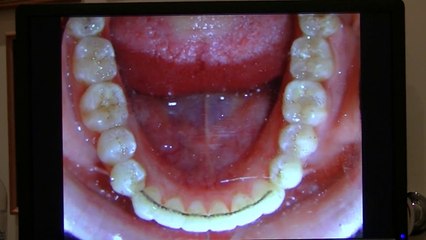

Invisalign Teen: NYC Orthodontist Case Study

() Here's an Invisalign Teen case study with NYC Orthodontist Dr. Stoess-Allen at her Park Avenue Orthodontics office.